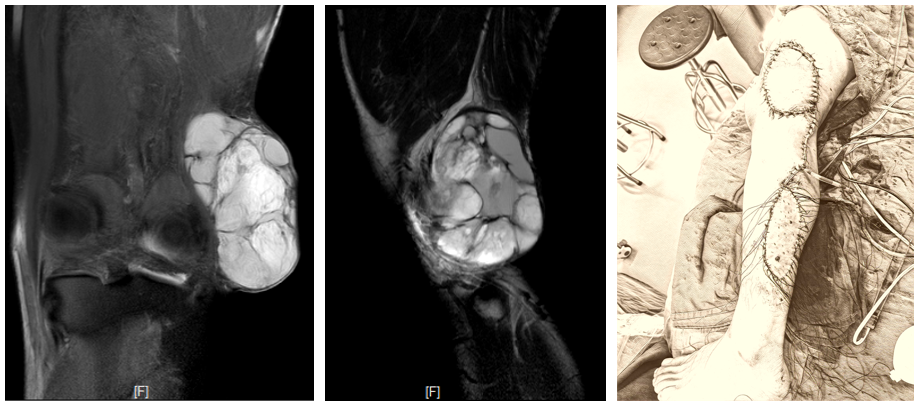

案例三 左膝外侧粘液纤维肉瘤(术后复发),行左膝肉瘤扩大切除,膝关节外侧软组织缺损,采用腓肠肌外侧肌皮瓣转移和取皮植皮修复创面。